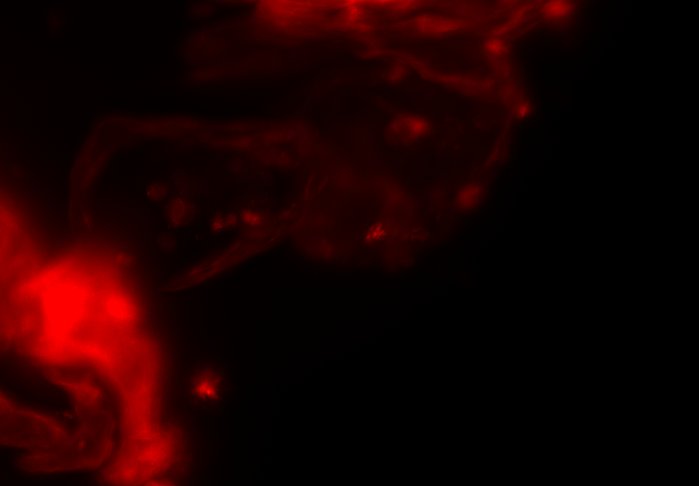

The combination of prospective optical gating for real-time phase matching and prospective optical gating for long-term phase locking allow us to capture in phase images over extended periods of times. Figure 4 demonstrates this phase locking over 18+ hours across a key developmental phase - heart looping.